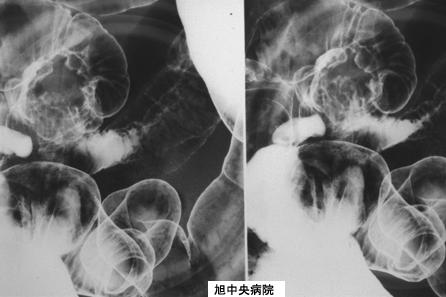

clasificación del pacienteLesión que asemeja tumoración/Endometriosis

parte(separada por órganos)intestino delgado/ileón

método de exámenRayos X

diámetro mayor del tumor35 - 40